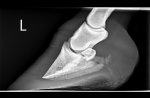

X-rays showed nothing too concerning, thankfully. No sinking, 6degrees rotation on bad foot and 4 on other, but given how sore she is, vet was very relieved and prognosis is good.